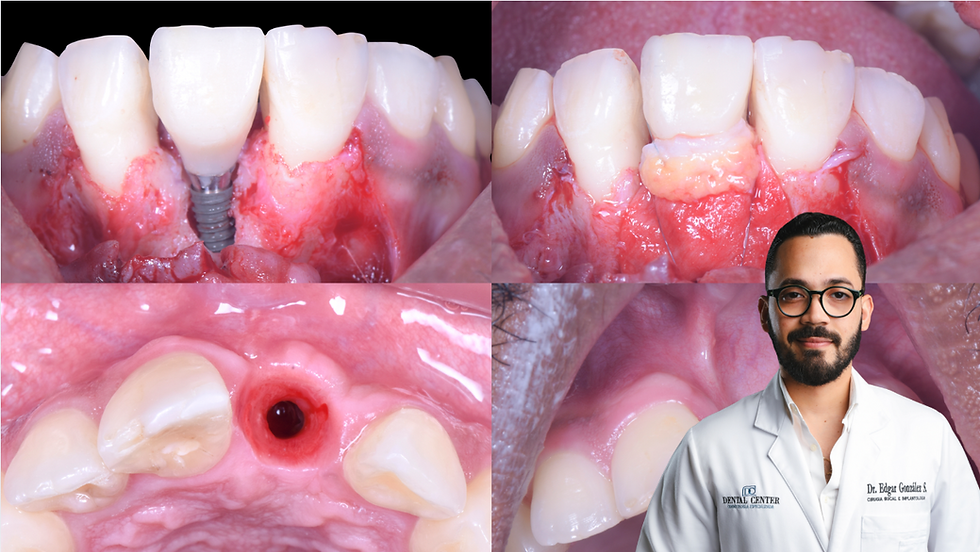

The treatment plan was a simultaneous IS-II implant placement with a Guided Bone regeneration with a A3 titanium membrane and a xenograft, covered by membranes by Plasma Rich in Growth Factors.

4 months later, the patient presented a soft tissue fenestration with a titanium membrane exposure.

At the time of membrane removal, we found good bone volume enough to continue with the procedure.

In order to resolve the soft tissue defect and prevent a bone infection, we opened the flap then removed the titanium membrane and we took a connective tissue graft from palate.

Placement of connective tissue graft under the flap in order to cover the bone and fill the holes left by the soft tissue fenestration.

Implant stability of 73 checked by Any Check at the time of membrane removal and implant uncovering.

One week healing

One month healing